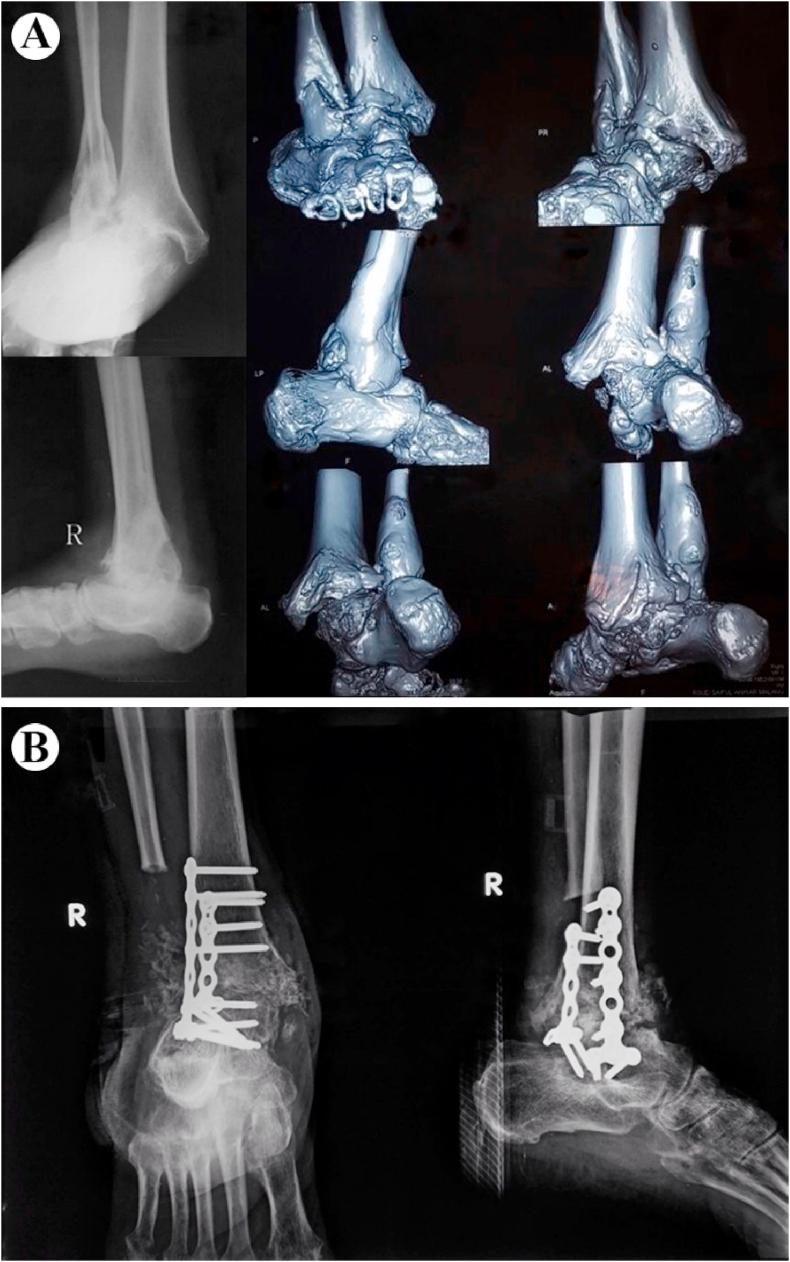

Ankle arthrodesis is one of the managements for a significantly unstable Charcot ankle. Some of the methods of internal fixation for ankle arthrodesis include the use of intramedullary nails, screws, and plates. Ankle arthrodesis using intramedullary nails has become more popular. However, studies evaluating the use of plate fixation, particularly double posterior lateral plating, are limited. We report the clinical and radiological outcomes of double posterior lateral plating ankle arthrodesis in three diabetic Charcot ankle patients.

Three patients, aged 73, 67, and 65 years old, complained of ankle pain and with a history of type 2 diabetes mellitus. The physical examination revealed swelling and erythema without a sign of active infection. The radiological examination showed ankle deformity, and the American Orthopaedic Foot & Ankle Society (AOFAS) Ankle-Hindfoot scores were 5, 10, and 0, respectively. All patients were diagnosed with a diabetic Charcot ankle and underwent ankle arthrodesis using double posterior lateral plating. Four months and six months follow up revealed talus union, improved ankle deformity, and improved AOFAS Ankle-Hindfoot scores to 70, 76, and 73, respectively.

Various methods of ankle arthrodesis are retrograde intramedullary nails, screws, and plates. In this report, we opt for plate fixation because it allows for stable internal fixation, adequate compression, high angular stability, and a lower irreversible deformation in osteoporotic bone.

踝关节融合术是治疗严重不稳定型夏科氏踝关节的方法之一。踝关节融合术的一些内固定方法包括使用髓内钉、螺钉和钢板。使用髓内钉进行踝关节融合术越来越受欢迎。然而,评估钢板固定,特别是双后外侧钢板固定的研究有限。我们报告了三例糖尿病性夏科氏踝关节患者采用双后外侧钢板固定踝关节融合术的临床和放射学结果。

三名患者,年龄分别为73岁、67岁和65岁,主诉踝关节疼痛,有2型糖尿病病史。体格检查发现肿胀和红斑,无活动性感染迹象。放射学检查显示踝关节畸形,美国矫形足踝协会(AOFAS)踝-后足评分分别为5分、10分和0分。所有患者均被诊断为糖尿病性夏科氏踝关节,并接受了双后外侧钢板固定的踝关节融合术。随访4个月和6个月时,距骨愈合,踝关节畸形改善,AOFAS踝-后足评分分别提高到70分、76分和73分。

踝关节融合术的各种方法包括逆行髓内钉、螺钉和钢板。在本报告中,我们选择钢板固定,因为它能提供稳定的内固定、足够的加压、高角度稳定性,并且在骨质疏松性骨中产生较低的不可逆变形。